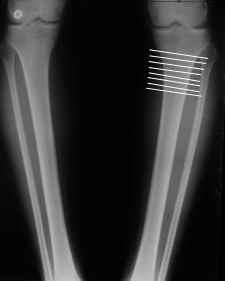

AC> Обратилась дама 25 лет. Вынуждена ходить в брюках из-за genu varum,

AC> что побудило обратиться за коррекцией.

Сейчас это модно (в смысле косметическая коррекция)... Хотя, судя по фото - в данном случае енто вполне оправдано...